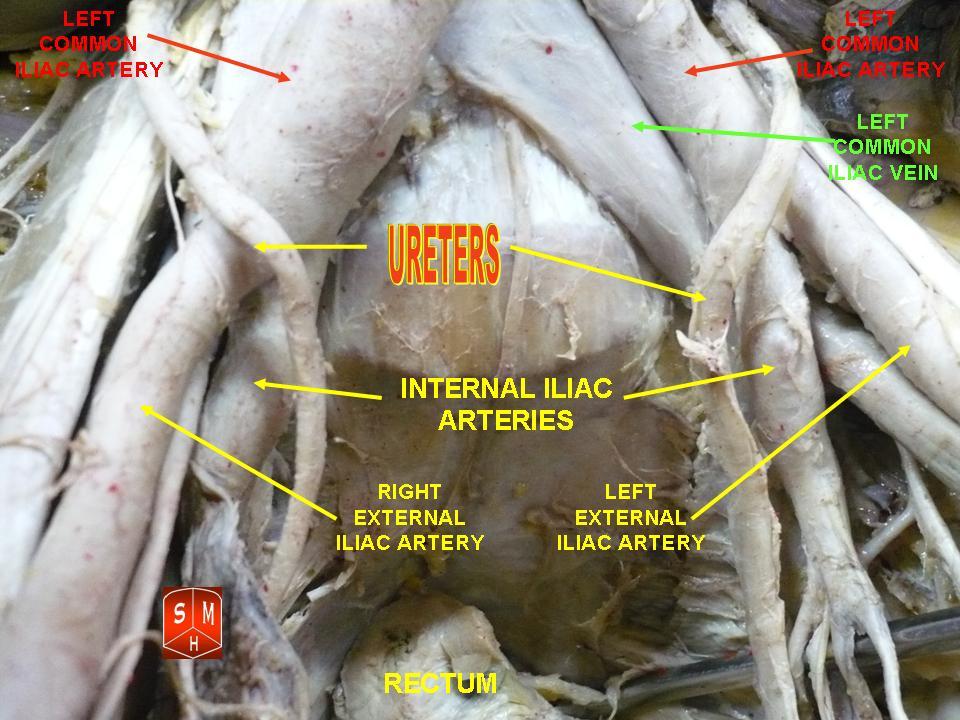

요관은 어른의 경우 약 20cm 길이의 관 모양의 구조로, 각 신장의 신우에서 방광으로 연결된다.[15] 신우에서 시작하여 요근 위로 내려가 골반 가장자리에 도달하며, 총장골동맥 앞에서 교차한다. 그런 다음 골반 측면을 따라 내려가 마지막으로 앞으로 굽어 방광 뒤쪽의 좌우에서 방광으로 들어간다.[1] 요관은 지름이 1.5mm이며,[15] 방광에 들어가기 직전 끝 부분에서 1cm의 평활근 층으로 둘러싸여 있다.[1]요관은 방광 뒤쪽 표면에서 들어가 슬릿 모양의 '요관 구멍'에서 바깥쪽 뒤쪽 표면에서 각도를 이루며 방광으로 들어간다. 요관은 1.5cm 이동한다.[1][2] 이 위치는 방광요관 접합부라고도 한다.[3] 수축된 방광에서 요관 구멍은 약 25mm 떨어져 있으며 내요도구와 비슷한 거리에 있다. 팽창된 방광에서는 이러한 측정값이 약 50mm까지 증가할 수 있다.[1]

요관이 신장에서 방광으로 내려가는 경로에서 요관 위, 옆, 주변을 통과하는 여러 구조가 있다.[1] 윗부분에서 요관은 요근 위를 지나고 복막 바로 뒤에 위치한다. 요근을 따라 내려가면서 생식대퇴신경 위를 지난다. 하대정맥과 복부 대동맥은 각각 오른쪽 및 왼쪽 요관의 정중선에 위치한다.[1] 복부 아랫부분에서 오른쪽 요관은 하부 장간막과 말단 회장 뒤에 위치하며, 왼쪽 요관은 공장과 S상 결장 뒤에 위치한다.[1] 요관이 골반으로 들어가면 결합 조직으로 둘러싸이고 뒤쪽과 바깥쪽으로 이동하여 내장골동맥과 내장골정맥 앞에서 통과한다. 그런 다음 안쪽과 앞으로 이동하여 제, 하방광, 중간 직장 동맥을 가로지른다.[1] 수컷의 경우 정관 아래를 지나 정낭 앞으로 지나 삼각 부근의 방광으로 들어간다.[1] 여성의 경우 요관은 난소 뒤로 지나 자궁 광인대 아랫부분 정중선에서 이동한다. 짧은 부분 동안 자궁 동맥은 2.5cm 동안 위를 통과한다. 그런 다음 자궁 경부를 지나 안쪽으로 방광을 향해 이동한다.[1]